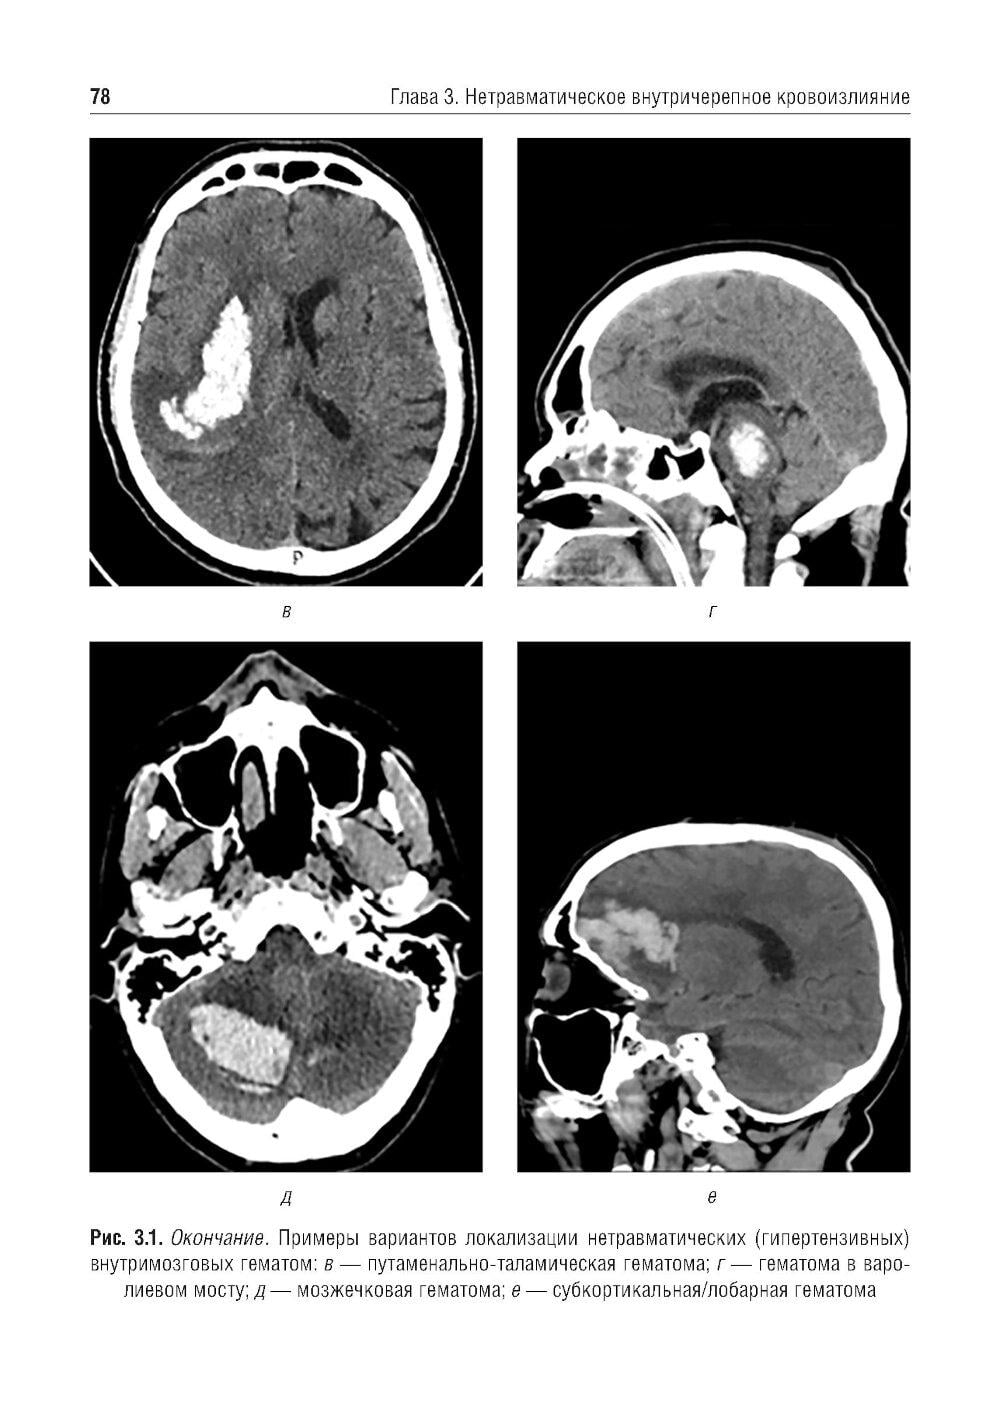

Учебное пособие составлено на основе действующих клинических рекомендаций. Представлены принципы формализованного подхода и формализованные шаблоны протоколов рентгеновской компьютерной томографии и магнитно-резонансной томографии при остром нарушении мозгового кровообращения и нетравматических внутричерепных кровоизлияниях.